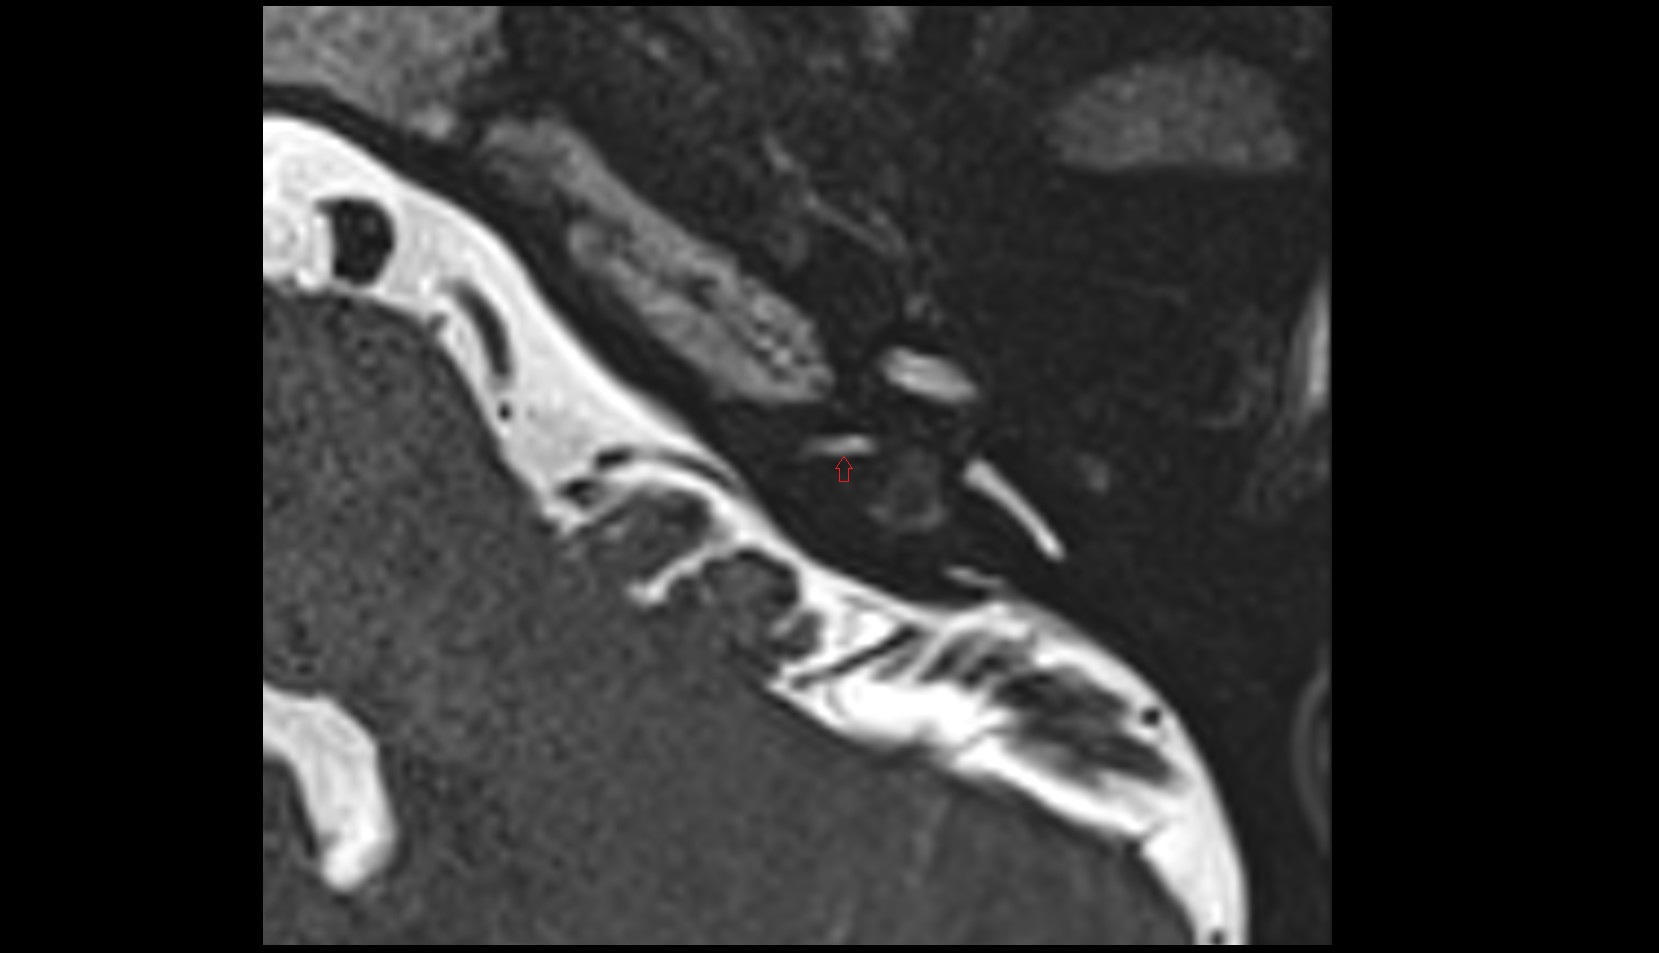

- Temporomandibular joint

- Mandibular condyle

- Mandibular fossa

- Articular disc of temporomandibular joint

- Articular eminence